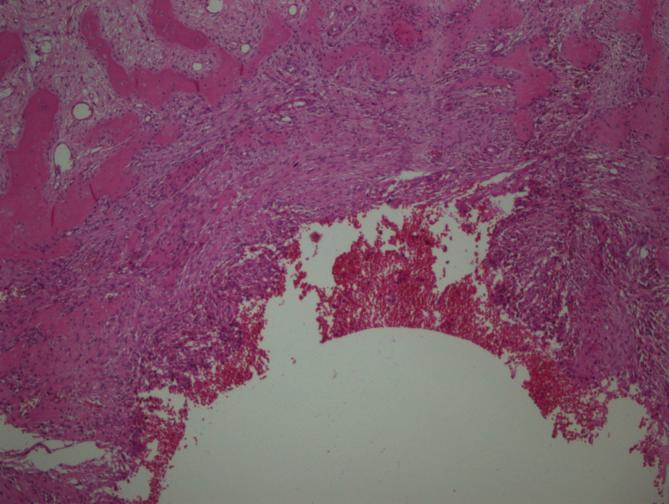

Tumors were localized most frequently at proximal tibia and distal femur, respectively. In 11 cases areas rich in fibrohistiocytic component and in 20 cases aneurysmal bone cyst like component were observed. In 2 cases both components were present. Twenty three cases recurred. In 1 case which was primarily located at calcaneus, tumor metastasized to lung 4 years later during follow-up.

GCT can be confused with other tumor or tumor-like lesions involving giant cells. Secondary changes such as fibrohistiocytic or aneurysmal bone cyst-like components and coagulation necrosis were frequently seen in conventional giant cell tumor of bone. For tumors having prominent fibrohistiocytic and/or aneurysmal bone cyst-like components, in order to detect characteristic areas representing GCT, additional sampling is essential. Although secondary histopathological changes do not appear to affect clinical outcome, these features are important in differential diagnosis. Approximately one fifth of GCT cases show recurrence and sacrum and foot bones were the most frequent sites for recurrence.

肿瘤最常分别位于胫骨近端和股骨远端。在11例中观察到富含纤维组织细胞成分的区域,20例中观察到动脉瘤样骨囊肿样成分。2例中两种成分均存在。23例复发。1例最初位于跟骨,随访4年后肿瘤转移至肺。

骨巨细胞瘤可能与其他涉及巨细胞的肿瘤或肿瘤样病变相混淆。在传统骨巨细胞瘤中,常见纤维组织细胞或动脉瘤样骨囊肿样成分以及凝固性坏死等继发性改变。对于具有显著纤维组织细胞和/或动脉瘤样骨囊肿样成分的肿瘤,为了检测代表骨巨细胞瘤的特征区域,额外取材至关重要。尽管继发性组织病理学改变似乎不影响临床结果,但这些特征在鉴别诊断中很重要。约五分之一的骨巨细胞瘤病例会复发,骶骨和足部骨骼是最常见的复发部位。